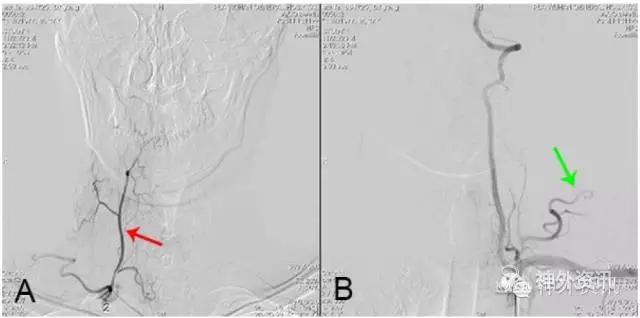

图14: 第三腰横静脉狭窄致脊髓静脉高压综合征A~C. MRI,红色↑示血管流空影;D、E. 第三腰横静脉造影,红色↑示左第三腰横静脉狭窄,绿色↑示向下腔静脉回流少,蓝色↑示向脊髓静脉回流;F. 球囊扩张治疗第三腰横静脉狭窄致脊髓静脉高压综合征,黄色↑示扩张球囊;G. 球囊扩张后,黑色↑示狭窄腰横静脉向下腔静脉回流通畅。